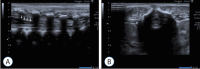

Objective: Ultrasonography (US) is the most non-invasive, safe, and, especially in the period of infancy, best method for visualizing and examining the spinal cord. Furthermore, US is the primary work-up for development of the spinal canal, and for follow-up on issues relating to subcutaneous tissues, bone development, and the spinal cord. Conus medullaris terminates at the second lumbar vertebra, according to a consensus in the literature.

Figures